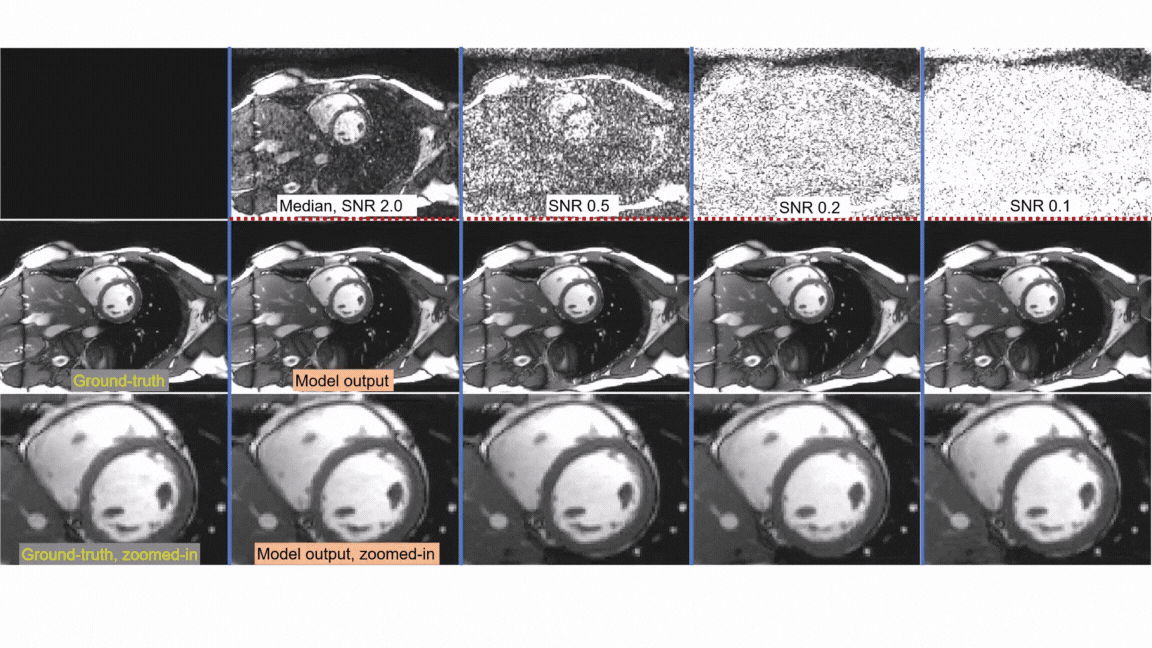

SNRAware: Improved Deep Learning MRI Denoising with SNR Unit Training and G-factor Map Augmentation

This research proposes a new training method, SNRAware, to improve the ability of deep learning models to denoise—or remove unwanted random variations—from MRI images. MRI images can suffer from high levels of noise when scanning is accelerated with parallel imaging or when data are acquired using lower cost, low-field MRI systems.

The researchers tested SNRAware on 14 different models, including ones based on transformer and convolutional architectures. The proposed training scheme improved the performance of all the tested models. This broad applicability means that the method is flexible and can be applied to different kinds of models without redesigning them. The testing showed SNRAware significantly improves the quality and clinical utility of MRI images while preserving important diagnostic details.

The movies correspond to the example in Figure 1b. The ground-truth clean image is the single one on the left.  The first row are the noisy samples. The second row are the SNR images.